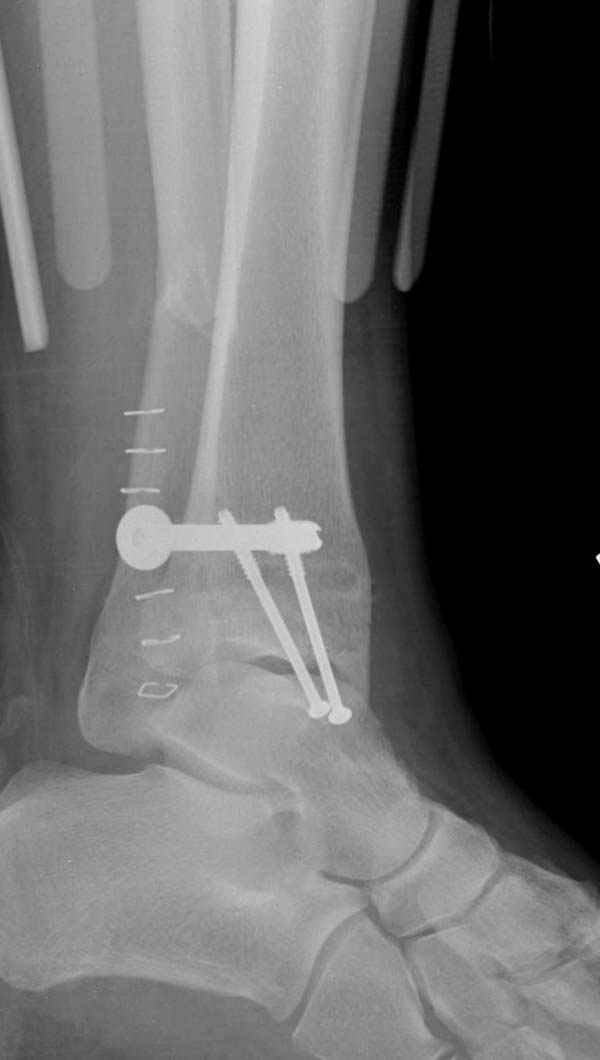

Если до сих ничего не сделано, с артродезом сустава в данный момент я бы повременил, на выставленных январских снимках хорошо сохранившийся сустав, а в "мортиз" (трехчетвертной) и на боковых снимках не менее 5 мм укорочение малоберцовой кости. Косые переломы лучше фиксировать пластинами, как то мы разбирали случай, где было отмечено, что это закон "таранная кость всегда следует за малоберцовой".

В данном случаи я бы уговорил больного на реконструкцию, для этого после удаления шурупов, спереди очистить от рубцов синдесмоз, несросшуюся наружную лодыжку - остеотомия по линии перелома и компрессирующий (lagging technique) кортикальный шуруп 3.5 мм по поперечнику остеотомии. Следующий этап - восстановление длины малоберцовой за счет удлинения, сделать поперечную остеотомию где-то на уровне сантиметр выше вашего синдесмозного шурупа, наложить длинную пластинку, прикрепить пластину за дистальный конец двумя или тремя шурупами; сохраняя контакт пластины с костью, имеющимся

compression&tension device AO system (при отсутствии любой lamina spreader подойдет, создать дистанцию между пластиной и шурупом, проведенным проксимальнее пластины) толкая проксимальный отдел пластины, низвести пластину, мортиз рентгенограмма подскажет на сколько. Если заранее сделать предоперационный план (ренгенограмма другой стороны), тогда точно можно определить, на сколько вам необходимо сделать поперечную остеотомию малоберцовой кости, для закрытия создавшегося дефекта.

Убедившись, что желаемая длина восстановлена, окончательная фиксация пластины, при этом через пластину пару 3.5 мм шурупов на синдесмоз, предпочтительно в четыре кортекса и оставить на 3 мм длиннее, если под нагрузкой синдесмотический шуруп сломается, сломанный конец легче удалить с медиальной стороны.

Медиальная сторона не в нагрузочной зоне, и там большая дыра - если есть 2.7 мм шурупы, или пару спиц в ваших условиях или методика Лазарева. Необходимо уделить внимание к мягким тканям, обнажается кость с латеральной стороны и у места где проводится остеотомия.